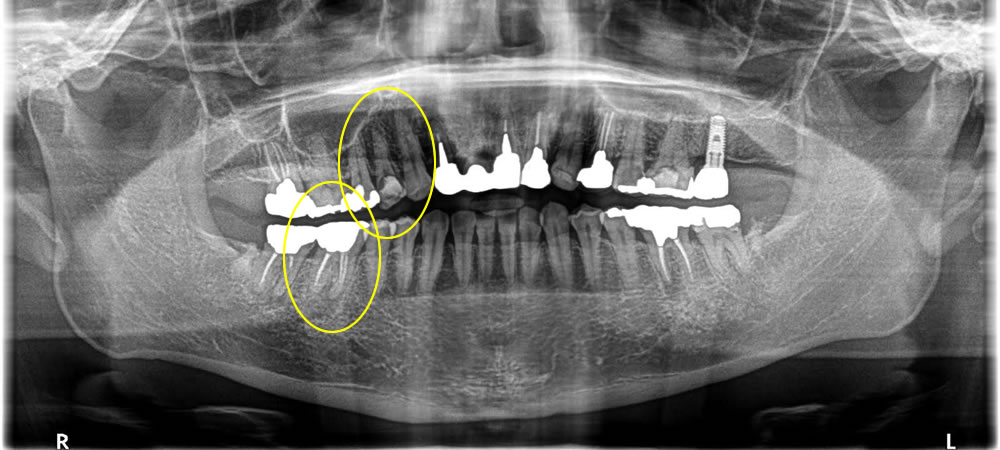

インプラント治療によって咬み合わせを回復した症例

年齢

50代

性別

女性

症例を見る